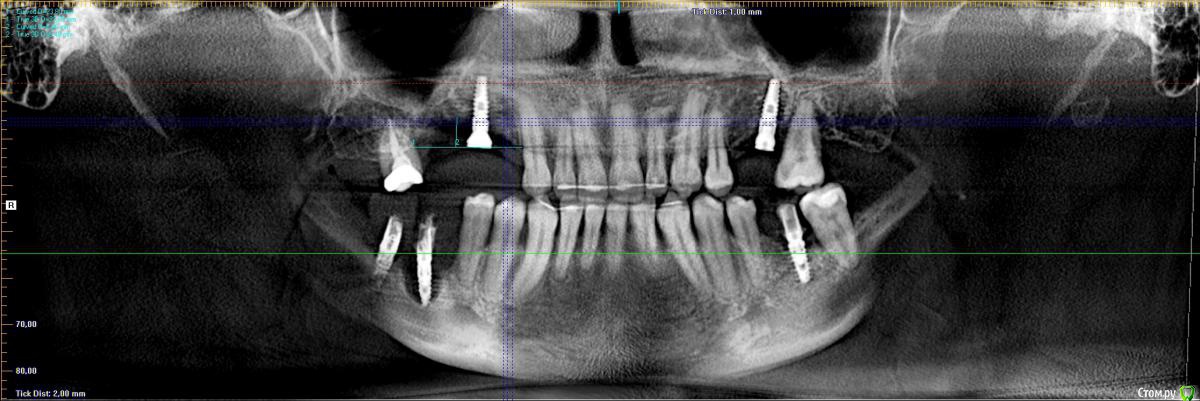

Тимур86 Опубликовано 25 февраля, 2020 Поделиться Опубликовано 25 февраля, 2020 Вот такая пациентка планируется.Интересует 1 сегмент,имлант уже удален,17 удаляем. Дефект как по горизонтали,так и по вертикали. НКР только горизонтально? Или вертикально тоже заморочиться? Ссылка на комментарий

Bier Опубликовано 25 февраля, 2020 Поделиться Опубликовано 25 февраля, 2020 ну ладно, ладно выдумывать Отвертикалить тут можно. Чтобы не увязнуть в рубцах, есть методы. Если зубы имеющиеся зубы нормальной высоты, я бы вертикалил. Ссылка на комментарий

stommm Опубликовано 26 февраля, 2020 Поделиться Опубликовано 26 февраля, 2020 Пики есть, вертикалить можно. Определите идеальную позицию имплантов от зенита коронок, померьте сколько не хватает по высоте если ставить в зонах где кость выше и от этого отталкивайтесь. Ссылка на комментарий